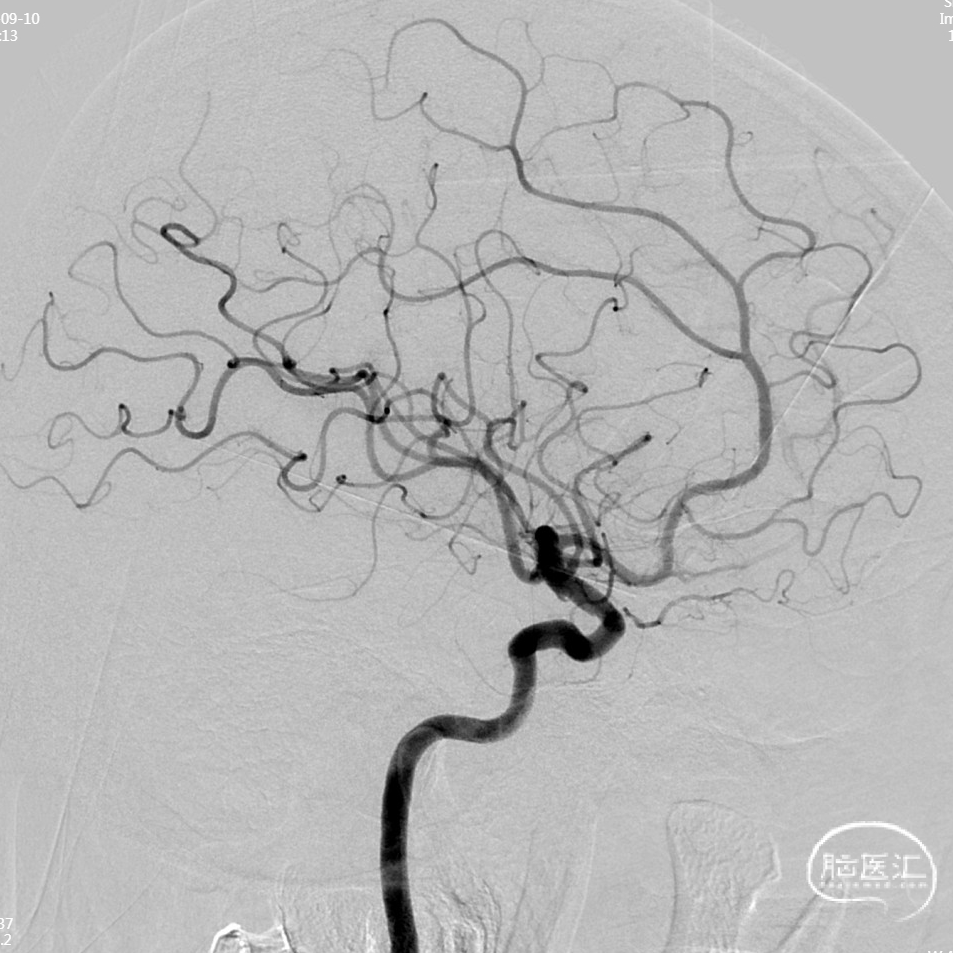

MRA:左侧大脑中动脉M1中远段及M2近段中度-重度狭窄,M2-4段明显纤细,分支明显减少。

左侧大脑中动脉M1段重度狭窄:

左侧M1段狭窄3D:

脑灌注成像(CTP)示:左侧额顶颞枕叶上述异常灌注,考虑脑梗塞周围缺血低灌注区。

气管插管全麻下经皮穿刺行左大脑中动脉M1狭窄段球囊扩张并支架植入。

本病例难点在于左侧大脑中动脉狭窄段结构复杂,DSA提示狭窄段上下壁均有对比剂缺失,病变远端分叉是M2起始段,选择上、下干有重要的考量,结合斑块病变累及下干,微导丝置于下干,球扩及支架覆盖狭窄病变段。

支架释放后造影: